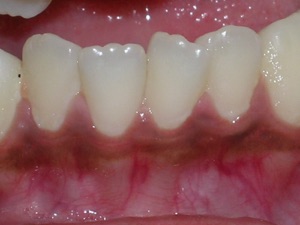

Some nice after photos.